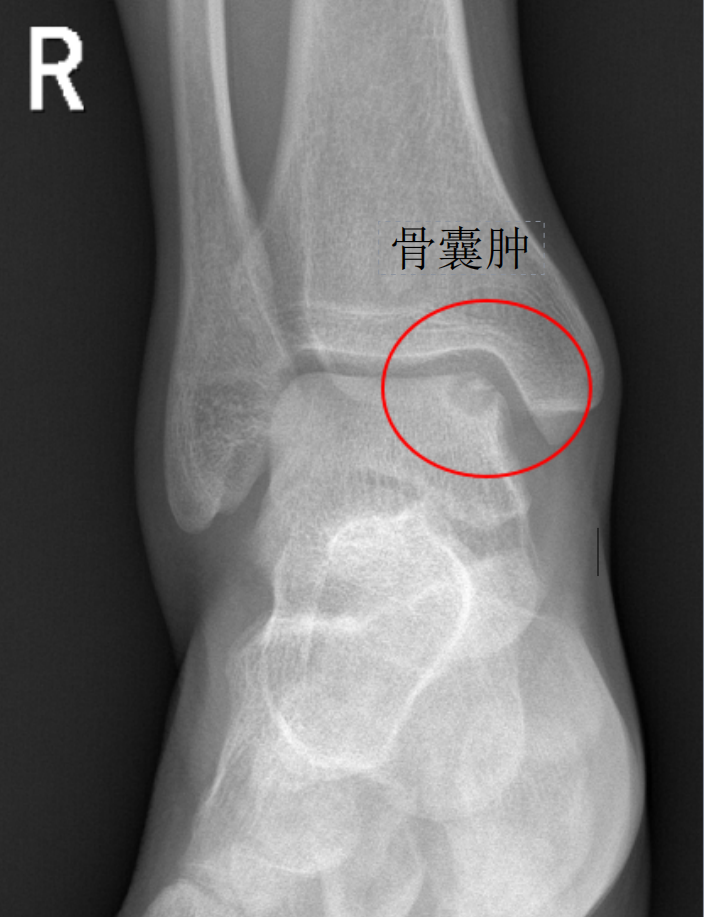

经查体,该患者右踝关节前抽屉试验阳性,内翻应力实验阳性,前外侧关节间隙压痛。踝关节距腓前韧带失效,踝关节不稳明显。完善踝关节DR及MRI检查。

根据病情决定行关节镜下右踝关节腔探查清理+外侧副韧带修复+距骨病灶清除+自体骨软骨移植术。